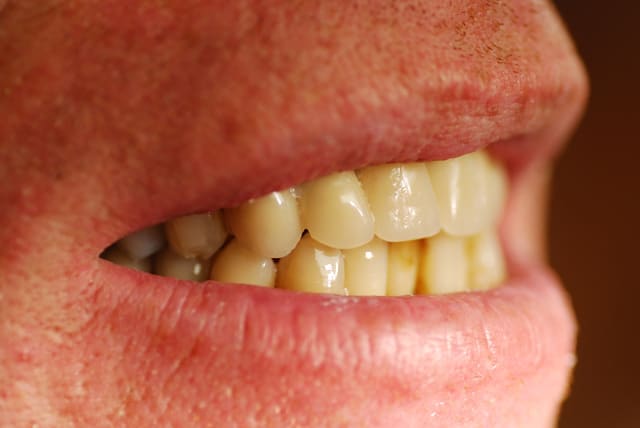

Je viens de revoir le patient et je peux vous apporter quelques précisions ainsi que des photos( désolé si la qualité n'est pas parfaite).

Patient de 45 ans, fumeur, motivé mais ne pouvant se payer d'implants.

Il a déjà vu plusieurs confrères qui lui ont proposé uniquement ( selon ses dires) une solution implantaire pour 12-11-21-22-23. Il souhaite du fixe...

En ce qui concerne la paro, la 12 est en mobilité stade 2, la 22 en stade 1 les autres étant non mobiles. Le sondage de 12 à 22 est de 3 mm, sauf en mésiale de 12 ( 6mm). La gencive est inflammatoire ( logique à la vue de l'inadaptation des couronnes, et des caries radiculaires).

Une photo du sourire peut t'aider à savoir si l'esthétique " rose" est primordiale ou non chez ton patient; si il a un sourire gingivale, vous allez en chier pour l'améliorer.

La 23 est hyper moche, la 12 encore plus...